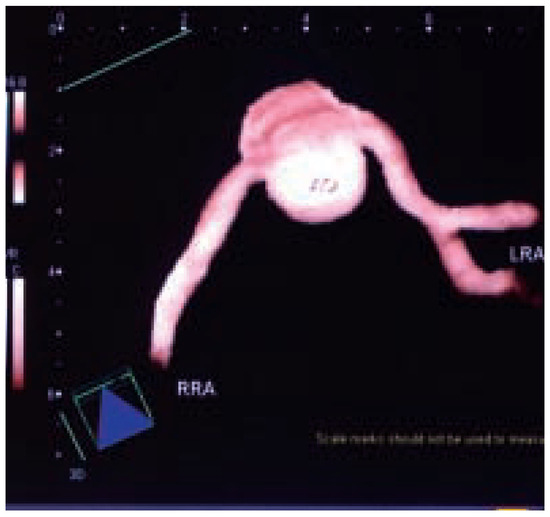

Dreidimensionale Angiosonographie

by Michel Zuber

Viele Gefässsysteme lassen... Full article

Show Figures

Figure 1